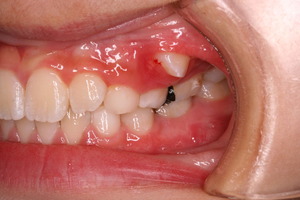

初診時はひどい状況でした。

まず、歯列矯正治療以前に虫歯の管理がまったくされておりませんでした。

年齢は7歳 小学校2年生ですので、 本来なら上下前歯が大人の歯に生えそろい、横の部分は乳歯がすべてある状況です。 いわゆる生えかわりの安定期という時期ですが、この患者さんはすでに何本か乳歯を抜いてしまっております。

また、下の前歯の歯肉も下がってきており、グループ的には1に属するものの、この悲惨は口腔内環境下では、矯正治療をおこなっても散々な結果になることが予想されました。

経過をみていくと、変な部分から大人の歯が生えてきました。

乳歯列時期に重篤な虫歯になった場合、あとから生えてくる永久歯は変な場所から生えてくることが多々あります。